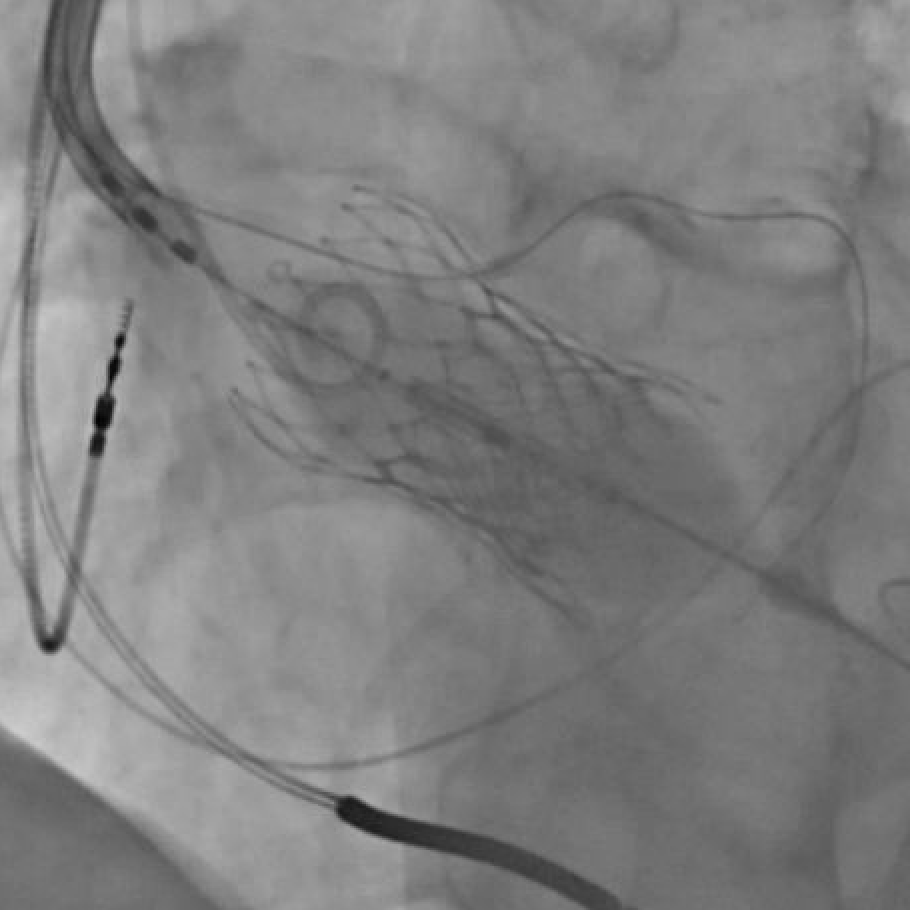

As some have identified, this valve was in-folded. We successfully retrieved the valve and put in a new one. I want to expand on this issue a bit. 🧵

Would you release this 34 mm Evolut? Why or why not? @GuiAttizzaniMD @djc795 @akcmahi